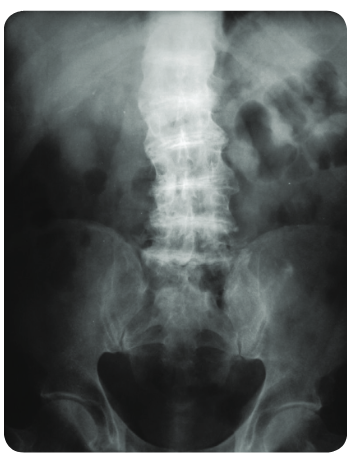

24 Qs1. A 50-year-old man comes to the clinic for evaluation of chronic back pain. He works as a librarian and notes that the pain is localized to his lower back and worsens after a long day of standing. The pain has not improved despite treatment with ibuprofen. Past medical history is significant for osteoarthritis of his right hip, for which he underwent a total hip replacement 2 years ago. Family history is noncontributory. Temperature is 37.0°C (98.6°F), pulse is 86/min, respirations are 16/min, and blood pressure is 125/85 mmHg. Ophthalmic examination reveals a bluish pigment deposition in the sclera. Dermatological examination reveals hyperpigmentation in the axillary and inguinal regions. Range of motion at the spine is limited. An x-ray of the erect spine is shown below:

Laboratory evaluation reveals elevated levels of homogentisic acid. The production of which of the following end products is likely to be inhibited, considering the most likely diagnosis?